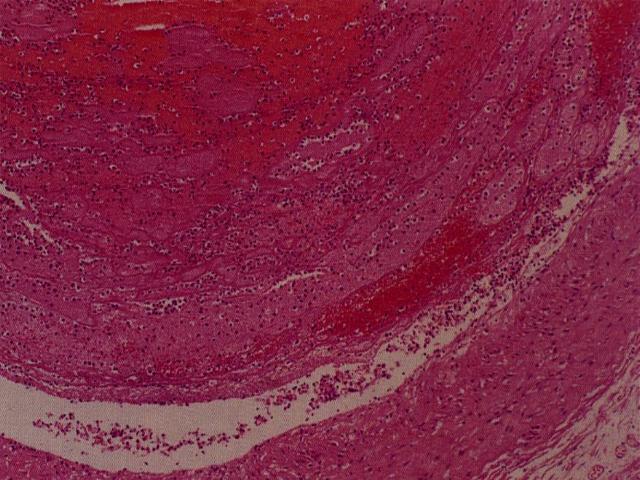

La hipertensión pulmonar es el evento final del edema pulmonar, ARDS o TEP, cuando se ha superado la gran distensibilidad del territorio vascular del pulmón. También patologías asociadas a severa hipoxia, producen por vasoconstricción, hipertensión pulmonar como el enfisema o enfermedades restrictivas. La célula endotelial del capilar pulmonar es la responsable de esta patología y refleja un daño celular reversible con la secuela de disfunción celular. Existe un forma menos frecuente de hipertensión pulmonar, que es la forma ideopática o primaria. La importancia de esta patología es que permite estudiar al disfunción de la célula endotelial fuera del contexto de patologías crónicas de larga evolución, responsables de la hipertensión pulmonar secundaria (edema, ARDS, TEP). En este contexto se ha descrito asociación a patología autoinmunitarias o de exagerada liberación de moléculas con acción vasoconstrictora como endotelina. También se ha postulado un rol de las células musculares lisas de la pared vascular y el vasoespasmo. Histológicamente las lesiones vasculares de la hipertensión pulmonar son variadas y no existe una morfología característica de las HTP 1ria o 2ria., sugiriendo que ambas podrían tener una patogénesis común. Una representación esquemática de la morfología en etapas temprana y tardía de la HTP se muestra en la figura [imagen]. La presencia de hipertrofia de la capa muscular [imagen] y la proliferación plexiforme de la íntima [imagen] son morfologías centrales en la HTP.